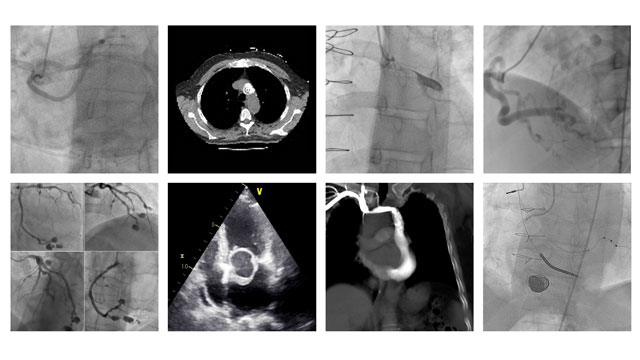

It has been said that the new imaging modalities are the “eyes of the Heart Team”. The critical importance of understanding imaging techniques and focusing awareness of their clinical implications cannot be underestimated. Here you can explore a selection of the most challenging, the most interesting, the most perplexing images from such diverse sources as EuroIntervention - images in cardiology or the PCR "An image is worth a 1000 words" competition.

To highlight the importance of imaging in interventional cardiovascular medicine, EuroIntervention shares it's most interesting images in cardiology.